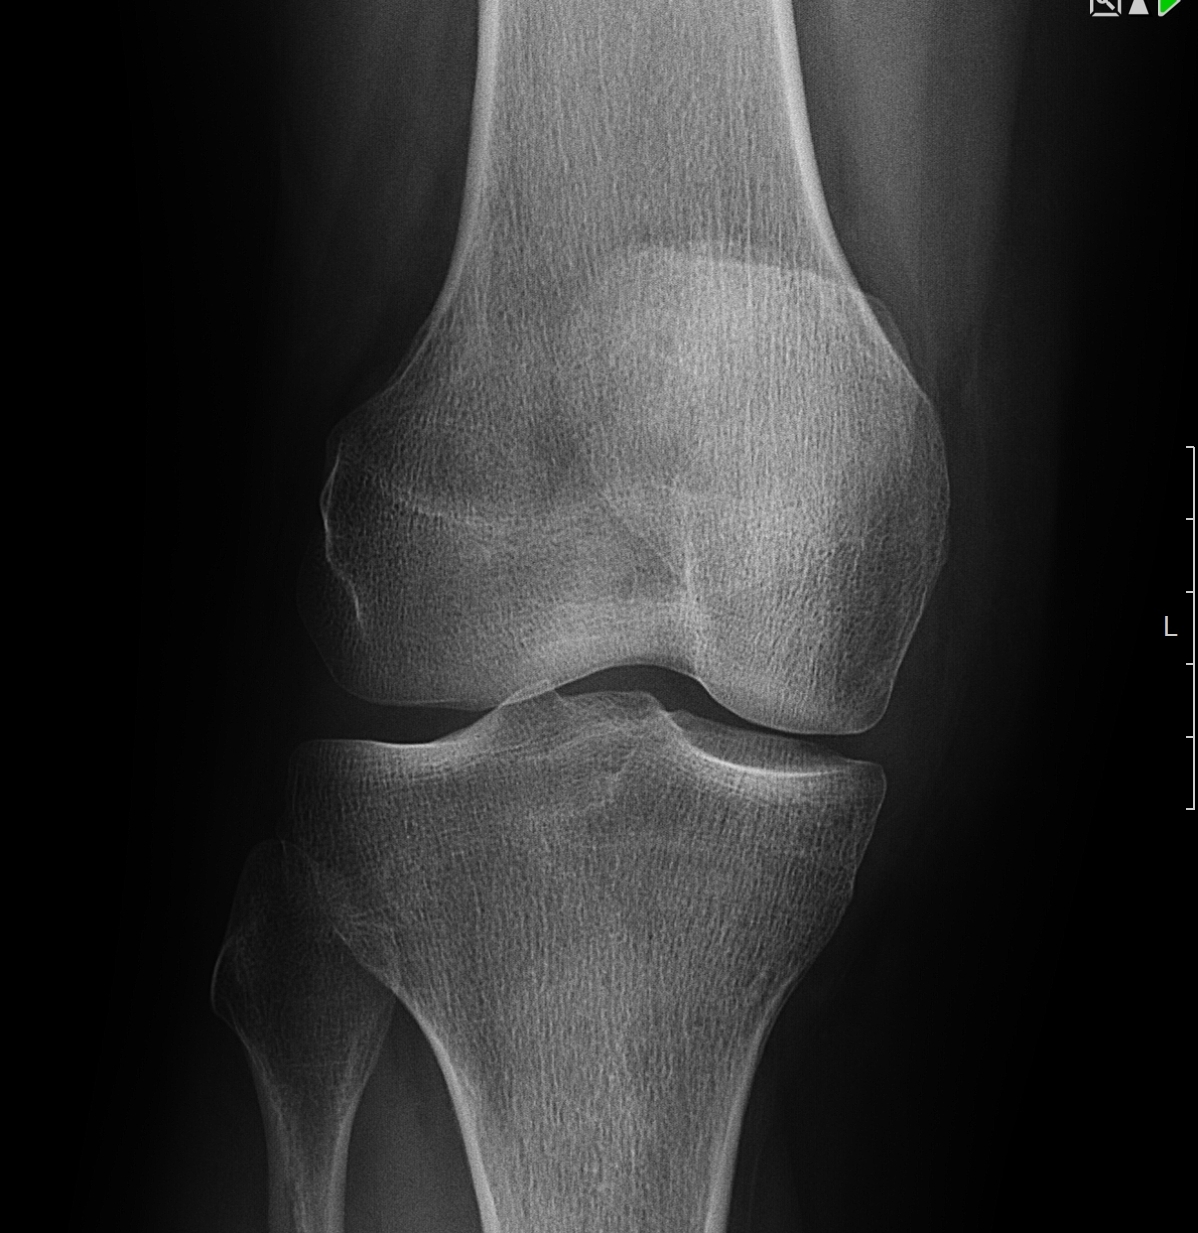

Рентгеновские снимки остеосклероза костной ткани